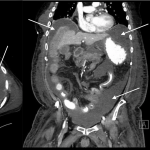

ABDOMINAL/PELVIC CT-SCAN WITHOUT IV OR ORAL CONTRAST

Key features of ascites seen in this imaging modality are:

- Density similar to water (transudative ascites): typically between -10 and + 10 HU

- Density slightly above water (exudative ascites): can be above 15 HU

The gallery below organizes examples of how ascites will appear on a abdominal/pelvic CT-scan without the usage of either IV or oral contrast. Click on the thumbnails below to open up the gallery: